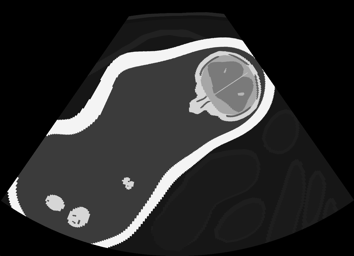

Real in-vivo images. 22 ultrasound sequences were collected using a GE Voluson E8 machine during standard fetal screening exams of 8 patients. Each sequence is several seconds long. We extracted all 4427 frames and resize them to , see Fig. 2 for some examples. The resulting image set was randomly split into training-validation-test sets by a 80-10-10% ratio.